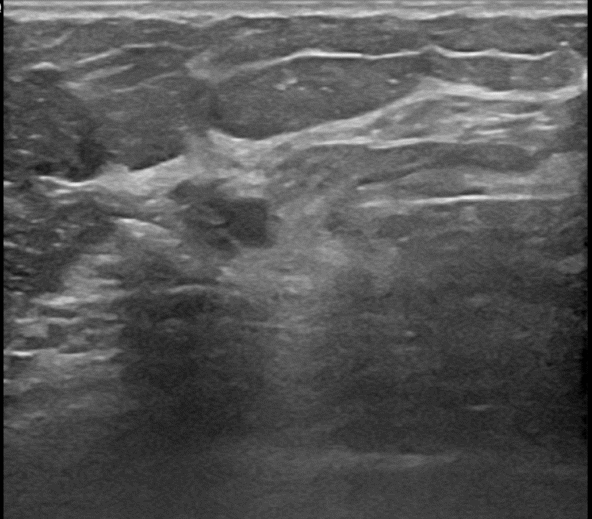

상기환자는 유방 통증으로 내원하신 60대초반

여성분으로 의심스러운 우측혹 조직검사 시행해 침윤성암으로 진단되었습니다